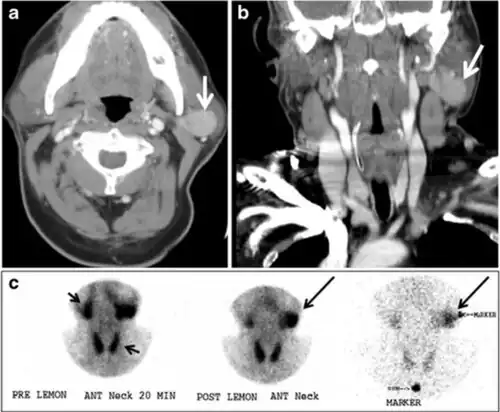

Fig. 17. Ectopic thyroid on the left parotid gland with a palpable left parotid mass in a 69-year-old male patient. a, b Axial and coronal enhanced neck CT scan demonstrates well-defined homogeneous enhancing mass (white arrows) within the left parotid gland with preserved surrounding fat planes. It also shows a normal thyroid in normal position in the lower neck. c Image taken 20 minutes after 5 mCi injected Tc99m-Pertechnetate shows normal thyroid uptake of tracer and physiological uptake in the salivary glands (short black arrow). There is a distinct focus of abnormal tracer accumulation in the left parotid/submandibular region. Patient was given lemon juice with evident normal washout from the salivary glands and relative retention by this abnormal focus (long black arrow).[1] -

Fig. 18. Lingular thyroid in a 33-year-old male who presented with oropharyngeal bleeding. an Axial enhanced neck CT scan at the level of mandible demonstrates a 3 × 3 × 3.4 cm round, partly well-delineated, heterogeneously enhancing lesion (white arrow). It is predominantly on the left side of the oropharynx and to some extent at the mid part of the base of the tongue. The thyroid gland was normal (not shown). b Image of the anterior face and neck taken 20 minutes after Tc99m-Pertechnetate injection shows absent thyroid radiotracer uptake in normal thyroid anatomical location (black short arrows). There is an area of increased uptake (long black arrows) corresponding to the posterior tongue mass identified on CT scan.[1]